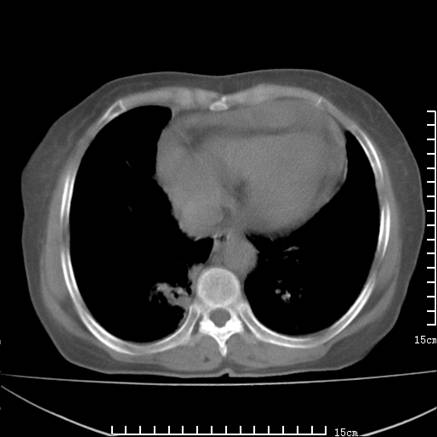

女,王某,58岁,咳嗽三个月余,基层医院二个月前诊为肺结核,用抗结核药二个月无明显疗效。

心包积液致肺瘀血.右侧周围型肺癌伴肺内转移,中间裂积液,叶间胸膜肥厚.右上肺大泡,右侧胸膜肥厚.

双肺继发型tb,心功能不全并肺淤血、心包、双侧叶间裂积液,肺大泡,右下胸膜肥厚钙化。